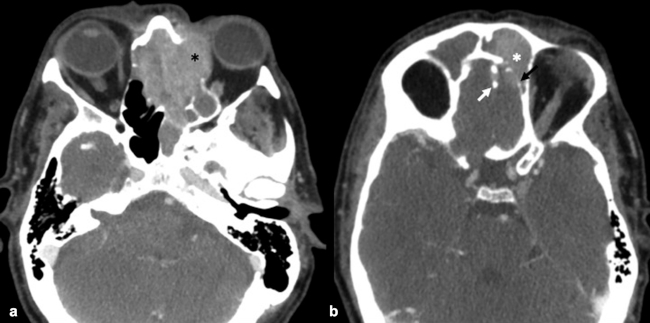

La TC de corte fino (espesor de corte de 1 mm) con reconstrucciones en plano coronal y sagital, es la mejor prueba de imagen inicial para el estudio del NBO. En la TC, aparece como una masa homogénea de tejido blando en la bóveda nasal con realce moderado y uniforme (►Figs.1y2). Se pueden encontrar calcificaciones punteadas dispersas (►Figs.2,3,4,5a,6).50 El valor principal de la TC es una mejor definición de la afectación ósea en comparación con la RM. La TC ayuda a evaluar la erosión ósea de la placa cribiforme, la fóvea etmoidal y la lámina papirácea (►Figs.1,2,3,4,5a,8). Sin embargo, la remodelación ósea sin erosión puede presentarse en algunos casos debido a su patrón de crecimiento indolente.3,35,49 Los estudios de TC generalmente revelan un patrón lítico y muy raramente hiperostosis dominante que simula displasia fibrosa.51 La TC también es útil para evaluar la presencia de metástasis regionales en cuello y a distancia.52,53

La RM es la prueba de imagen de elección para evaluar los detalles de la extensión y la estadificación locorregional del tumor. La RM es superior a la TC para determinar el grado de afectación del tejido blando (►Fig. 9) con una mejor evaluación de la afectación intracraneal (►Figs.10,11,12,13,14), orbital (►Figs.14y15), de la base del cráneo y la invasión perineural.53,54 La RM tiene un valor añadido para distinguir la afectación dural de la del parénquima cerebral (►Fig. 12).55 En la RM, el NBO aparece hipointenso respecto a la sustancia gris en imágenes ponderadas en T1 y de isointenso a hiperintenso en las imágenes ponderadas en T2 (►Figs.10,11,12,13,14,15).56 Muestra un realce homogéneo, excepto en áreas con hemorragia o necrosis. Además, permite diferenciar las secreciones retenidas del tumor, al ser estas hiperintensas ponderadas en T2.53,55 Los hallazgos de imágenes clásicos incluyen una masa “en forma de mancuerna” que se extiende a través de la placa cribiforme (►Fig. 12), con la parte estrecha a nivel de la placa. Los quistes tumorales periféricos (►Figs.5b,12,14,16) y las calcificaciones moteadas son bastante característicos de NBO.1